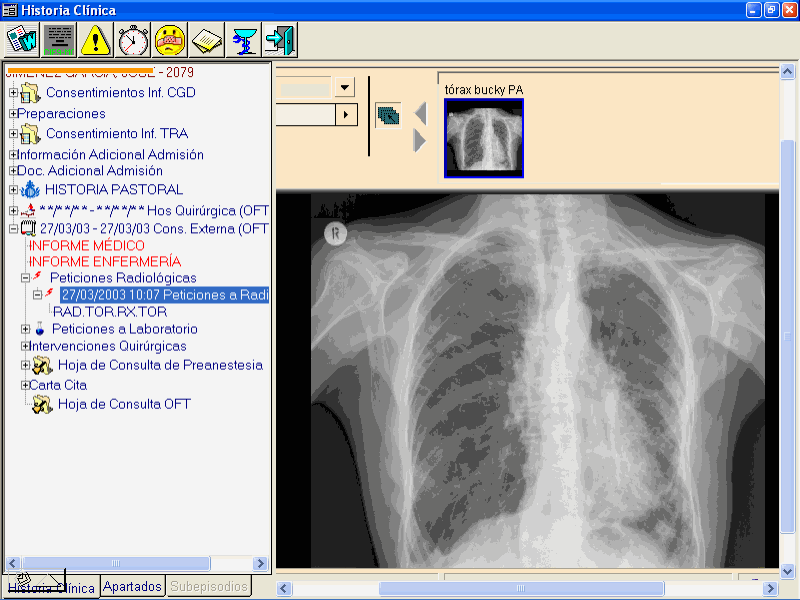

Siguiendo con el ejemplo del paciente al que le hicimos el plan de cuidados, se ve como queda toda la información disponible en MoviCare. Analíticas, Radiologías, o cualquier otra información de sistemas hospitalarios departamentales.

1.- Configuración y Mantenimiento de una Información Sanitaria integrada mediante el uso de arquitecturas de Información que faciliten el acceso pleno a la visualización y explotación de Resultados Médicos multidisciplinares.

-Configuración de "Motores" de integración para la optimización del enlace entre Atención Primaria y Especializada. El proyecto referido proporciona soluciones para facilitar:

=La coherencia de Datos entre SI (Primaria-Especializada)

=El proceso de Telecita entre áreas

=la devolución a Primaria de los Contenidos resultantes de la práctica especializada (Consultas, Resultados Médicos como Informes, Datos de Laboratorio, Imágenes Médicas, …)

=El Intercambio de Información y opcional Telecompartición "en tiempo real".